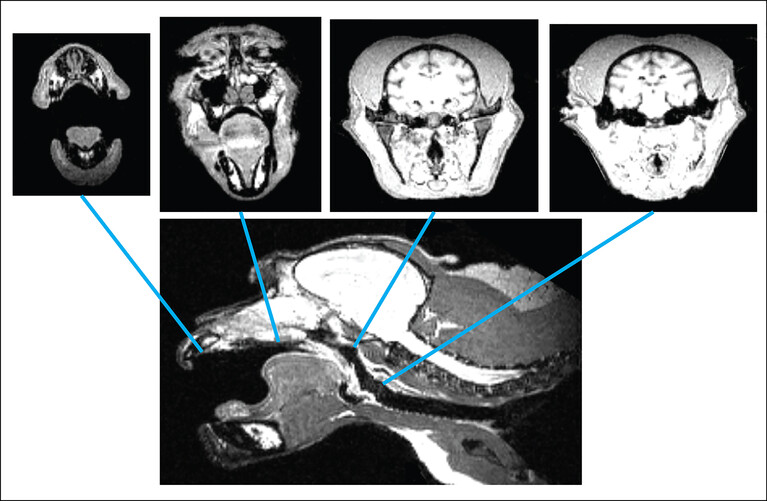

Bisher hatten Forscher gesagt, dass Affen nicht sprechen könnten, selbst wenn sie wollten, und hatten das mit den anatomischen Voraussetzungen begründet. Diese Daten wurden meist über Gipsabdrücke von toten Affen erhoben. Wissenschaftler aus den USA und Österreich haben für diese Frage jetzt zum ersten Mal lebende Affen untersucht, weil sie glaubten, dass der Sprechtrakt in Hals und Rachen viel flexibler ist, als es die Abdrücke von toten Affen zeigen. Wie die Forscher im Fachjournal Science Advances schreiben, haben sie Röntgenaufnahmen von Makaken gemacht, während diese Laute von sich gaben, schmatzten, kauten oder schlucken.

Die Forscher vermaßen so die Hohlräume in Mund und Rachen der Tiere. Sie folgern: Die Makaken wären anatomisch durchaus in der Lage, Laute zu erzeugen, die der menschlichen Sprache ähnlich wären. Die Forscher haben aufgrund ihrer Erkenntnisse auch eine Makaken-Stimme simuliert. So würde ein Affe klingen, wenn er auf Englisch einen Heiratsantrag machen würde: